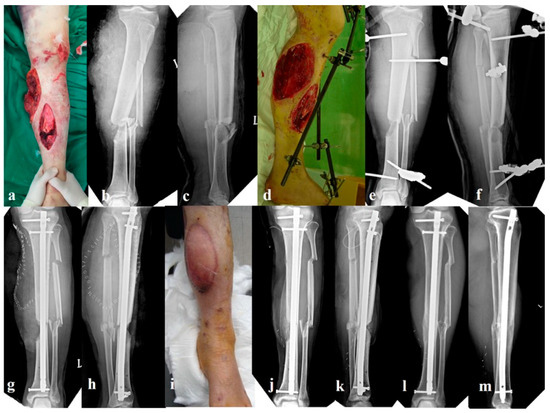

Provisional Reduction Plating Versus External Fixation in the Staged Management of Gustilo–Anderson Type II–III Open Tibial Shaft Fractures

by Yong-Cheol Yoon, Seok Hwan Yoon, Min Jun Kim and Hyoung-Keun Oh

J. Clin. Med. 2025, 14(23), 8421; https://doi.org/10.3390/jcm14238421 - 27 Nov 2025

Background/Objectives: Open tibial shaft fractures are severe injuries associated with high risks of infection and malunion. Although external fixation is commonly used for provisional stabilization, it provides limited control over alignment and soft tissue handling. This study aimed to evaluate and compare provisional [...] Read more.

Background/Objectives: Open tibial shaft fractures are severe injuries associated with high risks of infection and malunion. Although external fixation is commonly used for provisional stabilization, it provides limited control over alignment and soft tissue handling. This study aimed to evaluate and compare provisional reduction plating with external fixation for the staged management of Gustilo–Anderson type II–III open tibial fractures. Methods: Fifty-nine patients (mean age, 38.5 years) treated with staged debridement and delayed intramedullary nailing (IMN) were retrospectively reviewed. Thirty-two patients underwent reduction plating with external fixation (group A), and 27 underwent external fixation alone (group B). Clinical, radiographic, and functional outcomes, including infection, union, malunion, operative time, and Lower Extremity Functional Scale (LEFS) scores, were analyzed. Results: Deep infection and nonunion rates were comparable between the groups. Group A had fewer malunions (3.1% vs. 18.5%), shorter operative times, and faster progression to union than group B. The LEFS scores were higher in group A, indicating better functional recovery. Conclusions: Provisional reduction plating before IMN appears to enhance alignment, preserve soft tissue integrity, and improve surgical efficiency without increasing the risk of infection or delaying union. These findings suggest that it may be a safe and effective adjunct to the staged treatment of complex Gustilo–Anderson type II–III open tibial fractures. Full article

(This article belongs to the Section Orthopedics)

Show Figures

Figure 1